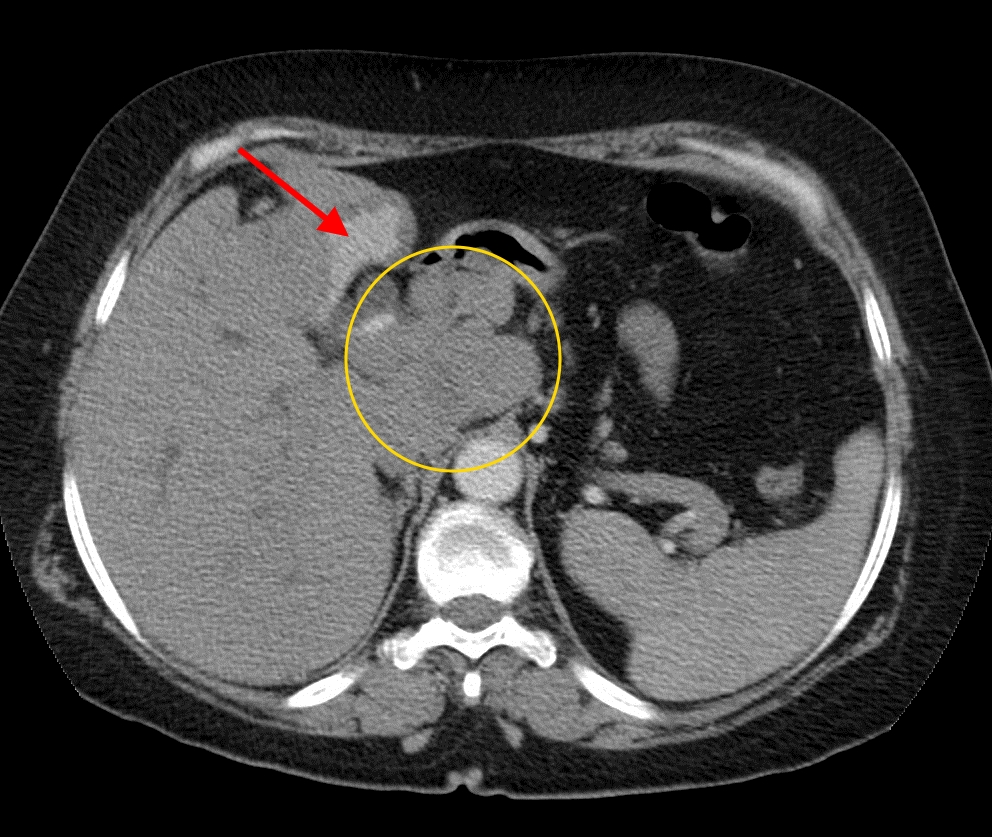

Рак поджелудочной железы на снимке КТ

Для успешного лечения онкологической патологии важно выявить новообразование на ранних стадиях развития. Для этого используются скрининговые методики исследования. С целью определения локализации, размеров и формы опухоли назначаются методики визуализации. К ним относятся рентген, компьютерная, магнитно-резонансная томография, ультразвуковое исследование. Оценка функционального состояния организма осуществляется при помощи лабораторных исследований, к которым относятся клинический анализ крови, мочи, биохимические пробы.